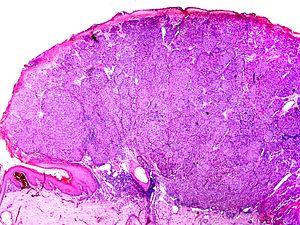

The microscopic hallmarks are:

• Dome-shaped at low power

• Epidermis thin or normal

• Dermal nodule of melanocytes with a 'pushing' growth pattern

• No "radial growth phase"